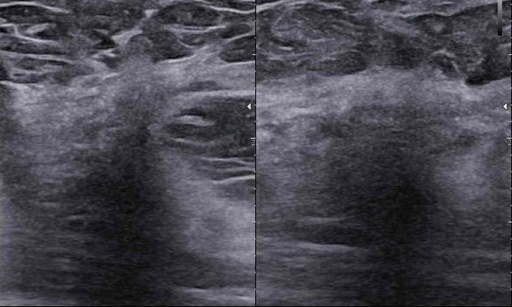

Rak piersi a obraz węzłów chłonnych. LN-RADS

Rak piersi a obraz węzłów chłonnych. LN-RADS - część 2